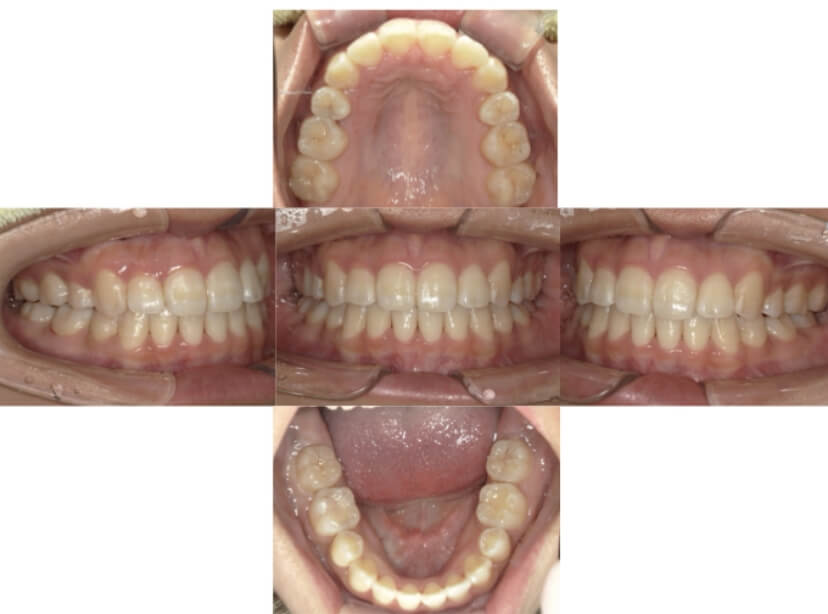

BEFORE

AFTER

症例1

上顎前突、叢生

抜歯

ブラケット矯正

上下顎叢生、上顎前突(出っ歯、上下の前歯のガタガタ)のケースです。

装置はラビアル(上下表側)で、上顎の小臼歯を2本抜歯を行っています。抜歯したスペースを使って、上の前歯の後方移動と叢生(ガタガタ)と出っ歯の改善を行っています。下は歯と歯の間にIPR(隣接面削合)を行い、スペースを確保し、叢生の改善を行っています。

主訴 前歯のガタガタと出っ歯が気になる。

年齢・性別 47歳 女性

お住まいの地域 神奈川県川崎市

治療方針 抜歯スペースおよびIPRを利用して上前歯の叢生(ガタガタ)の改善

抜歯部位 上顎左右第一小臼歯

使用装置 ラビアル(上下表側)、顎間ゴム

治療期間 2年0か月

治療回数 15回

リテーナー クリアリテーナー